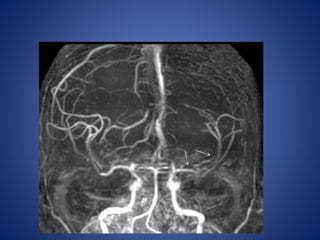

5 yrs male child with history of left sided focal seizures with secondary generalization

5 yrs malechild with history of left sided focal seizures with secondary generalization

Moya Moya

• Stenosis/occlusion of the distal ICA

• moyamoya vessels with signal voids in the basal ganglia

• ischemia

• infarction

• atrophy, and ventriculomegaly.

• Small abnormal net-like vessels proliferate giving "puff of smoke"

appearance.

• Contrast-enhanced T1WI - marked leptomeningeal enhancement

along the cortical sulci (ivy sign).

often show contrast stagnating in slow-flowing collateral

vessels both in the brain parenchymal and over its surface.

MR imaging